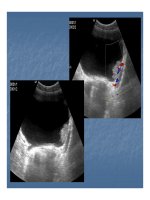

 Tràn máu, nước tiểu trong ổ bụng Tràn máu, nước tiểu trong ổ bụng  vỡ BQ trong vỡ BQ trong

phúc mạc.phúc mạc.